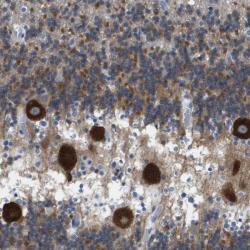

- Experimental details

- Immunohistochemical staining of human cerebellum shows strong cytoplasmic positivity in purkinje cells.

- Validation comment

- Two independent antibodies targeting one protein yielding similar staining patterns. Staining pattern consistent with experimental and/or bioinformatic data.